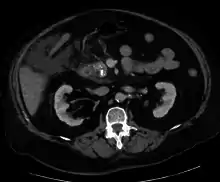

A contrast-enhanced CT scan is usually performed more than 48 hours after the onset of pain to evaluate for pancreatic necrosis and extrapancreatic fluid as well as predict the severity of the disease. CT scanning earlier can be falsely reassuring.